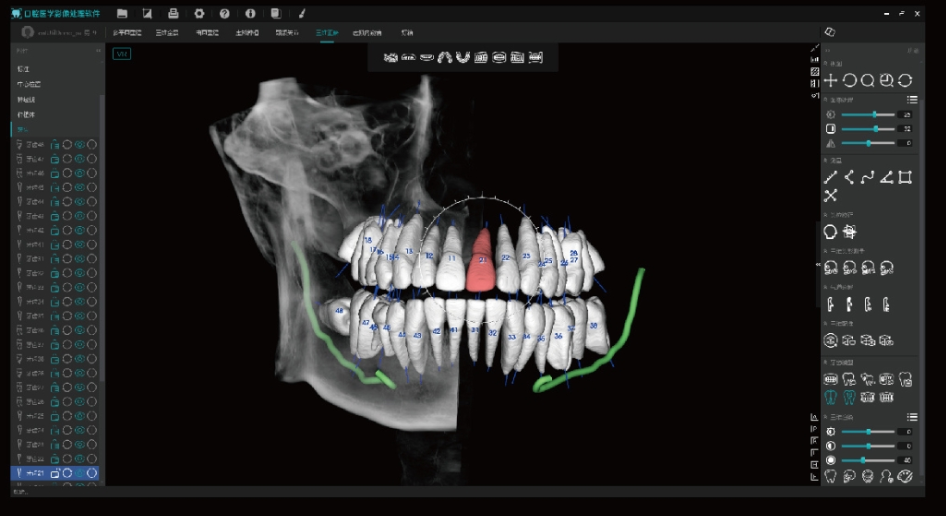

Modo maxilofacial

Modo maxilar y dental

Método de dentición

Ultra-clear display of the entire dental arch and jawbone structure.

Tecnologia Inovadora Root-Bone Glass

Suporta o posicionamento manual dos dentes, a remoção dentária e a observação tridimensional da câmara pulpar.

Permite o planeamento imediato de extrações e implantes.